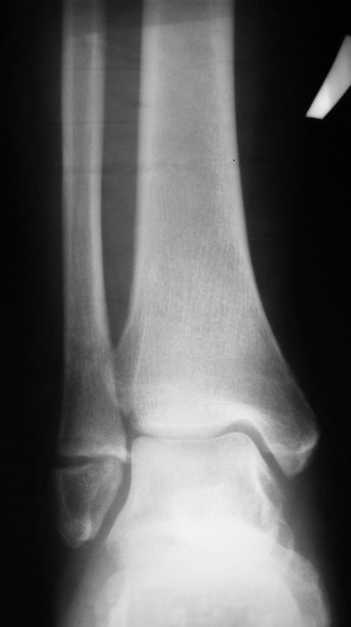

На одном из форумов заспорили о тактике.Женщина 23 года, рост 158, вес 55, профессия: менеджер, хобби: верховая езда, горные лыжи, велосипеды, не курит, сопутствующих заболеваний нет.28 июня упала с лошади.первый рентген:

Иммобилизация гипсовым сапожком до 20 августаНа сегодня- Гипс снаят, со слов больной "Наступать на ногу не больно, но страшно. Сустав и мышцы, конечно, плохо работают."

Вечер добрый! Судя по представленным рентгенограммам (с интервалом почти в два месяца!?) перелом не сросся. Лично я склоняюсь больше в сторону оперативного лечения (с учетом анамнеза пациентки). Но для принятия окончательного решения хотелось бы, для начала, увидеть снимки обоих суставов в сравнении в двух проекциях , а также сравнительные - фас под нагрузкой. При отсутствии жалоб со стороны пациентки на сегодняшний день (при данной рентгенологической картине), они (жалобы) ,скорее всего, появятся позже.

Показано оперативное лечение - металлоостеосинтез латеральной лодыжки маллеолярным винтом. Никаких признаков сращения на сегодняшний день не наблюдается. Непонятно, чем вызвана такая неопределённость врачей. В ортезе нагрузка на сустав на сегодняшний день не просто возможна - необходима.

Ничего удивительного в том, что мнения хирургов разошлись нет, поскольку в целом в мире разные хирурги исповедуют разные тактики лечения переломов наружной лодыжки. Так одни считают, что нужно оперировать даже при смещении в 1 мм, другие допускают 5 мм. В среднем считают «цифрой старта» 2-3 мм. Но все сходятся в том, что нужно ориентироваться на функциональные запросы пациента. Но в вашем случае уже не свежий перелом, а замедленная консолидация со смещением отломков. (Delayed malunion? :-{)

Андрей, я всё таки склонен считать, что принципиального разногласия нет. На сегодняшний день рекомендовать оперативное лечение меня заставили следующие факторы:

1. Увеличивающийся диастаз фрагментов,

2. Отсутствие на рентгеновских снимках признаков образования костной мозоли, с одной стороны и

3. Образование кортикальной замыкательной пластинки на проксимальном фрагменте в зоне контакта, с другой,

1- Диастаз увеличивается. За счет чего? Сам дистальный отломок наружной лодыжки как был на месте, так и стоял. Т.е. увеличение диастаза не за счет подвижности и нестабильности, а за счет резорбции.

Данный перелом по классификации Вебера относится к типу А- т.е. дистальнее синдесмоза. В этом месте малоберцовая кость не несёт никакой нагрузки. Прошло только 2 месяца с момента перелома дайте больной что-то типа Air cast на месяц-полтора и полную нагрузку на ногу и сгибательно-разгибательные движения в суставе.